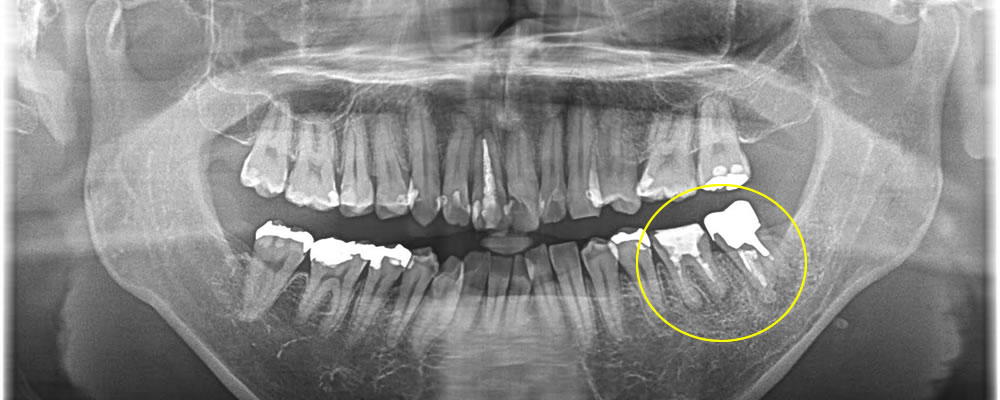

膿が溜まった歯を抜歯後にインプラントで治療した症例

こちらの患者さまは左下の奥歯が痛く、他院にて保存する事ができないと診断され来院されました。

CT検査にて根の先に大きく膿が溜まり、骨が溶けてしまっている事が確認されました。1番奥の歯と2番目の歯にも確認されましたが、患者さまのご希望により、1番奥の歯のみを抜歯し、インプラント治療を行う事になりました。